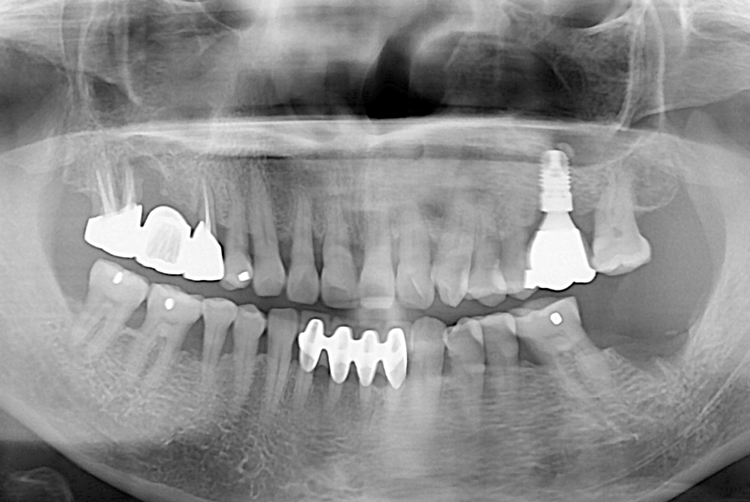

치료전 : 2016-11-23

18.02.28.jpg

치료후 : 2018-02-28

세종치과는 많은 환자와 다양한 케이스를 바탕으로 항상 편안한 임플란트 수술을 제공하고자 노력하고,

오래동안 튼튼히 쓸 수 있는 임플란트 수술을 가장 큰 목표로 삼고 있습니다